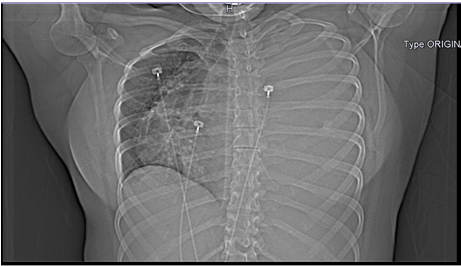

The patient underwent emergent chest tube placement with thoracoscopy. Adhesions were found seeding the right thoracic cage and adhering to the collapsed lung. Biopsy and lysis of adhesions allowed for lung re-expansion. Thoracoscopy allowed for drainage of 3700 mL of serosanguinous fluid under pressure from the left thorax, with an additional 220 mL drained in the hours following the surgery. Chest radiograph was obtained immediately after chest tube placement (Figure 3) to verify the positioning and severity of mediastinal shift and repeated on postoperative day (POD) 1. Computed tomography imaging on POD 4 revealed an increase in the mass’s size measuring 14.3 × 11.5 × 15.7 cm (Figure 4). Imaging also revealed a persistent but decreased mediastinal shift to the right with a hydrothorax. During the patient’s one-month admission, total drainage from the chest tubes totaled 15.929 liters of serosanguinous fluid.

Figure 3: Chest radiograph (CXR) imaging immediately following emergent exploratory thoracoscopy. Persistent but slightly less prominent mediastinal shift to the right is present. Mild subcutaneous air is noted along left chest wall, but no pneumothorax was appreciated.